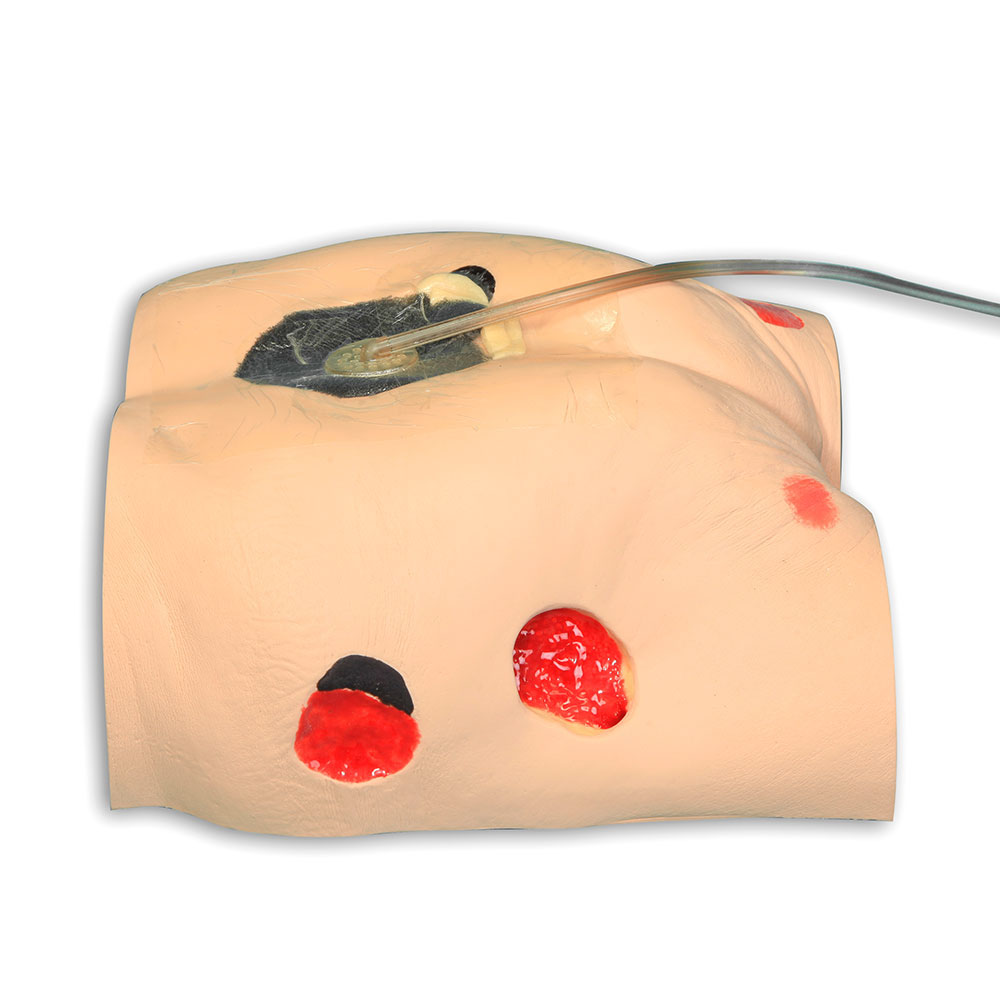

The Seymour II™ Wound Care Model is a highly realistic pressure injury simulator moulded from a 74-year-old patient. It accurately replicates the look and feel of human tissue and presents a wide range of pressure injuries, including Stages 1–4, DTPI, unstageable wounds, and a dehisced wound for advanced wound care training.

- Wound care simulation model displays the following pressure injuries:

- 5 ½” dehisced wound

- For use with negative pressure wound therapy devices (without adhesive residue)

- The Stage 3 and Stage 4 are positioned so that a “bridging” dressing for use with a vacuum-assisted closure and negative pressure wound therapy devices can be demonstrated and practiced

- Incredibly lifelike, most comprehensive model of its kind